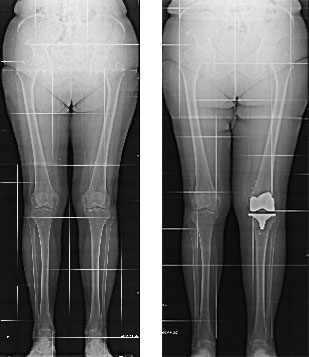

Paziente donna di 67 anni, affetta da gonartrosi tricompartimentale sinistra aggravata da calcificazione dei menischi, trattata con protesi totale mini invasiva del ginocchio a conservazione del legamento crociato posteriore.